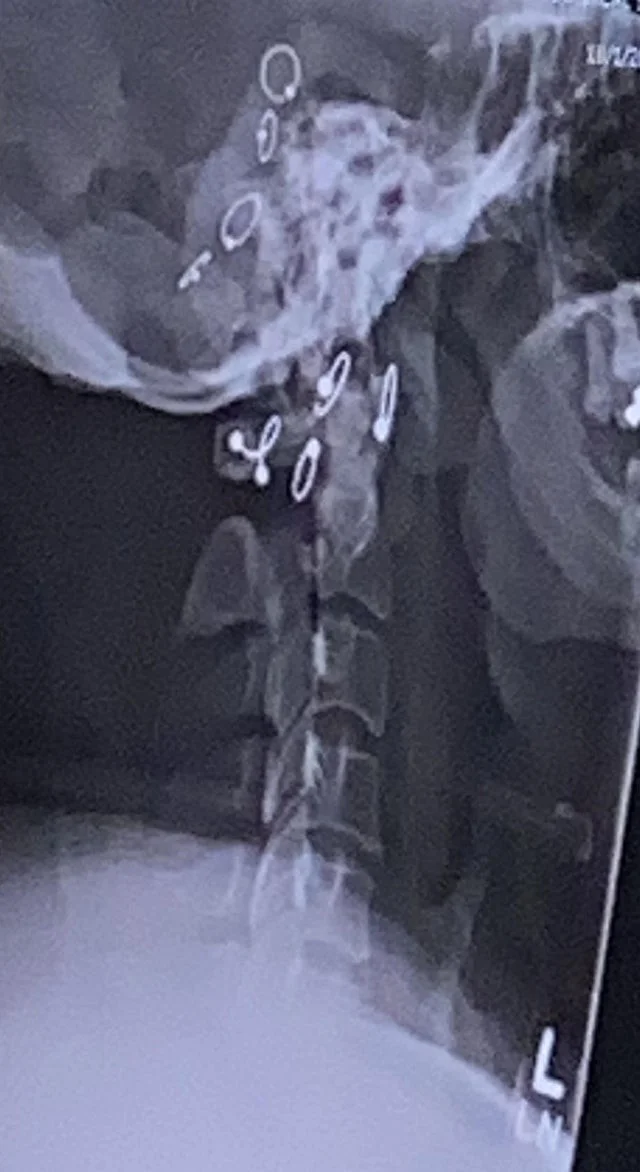

Просто пирсинг в носу

Сережки на снимке

Любые ожерелья лучше снимать перед исследованием